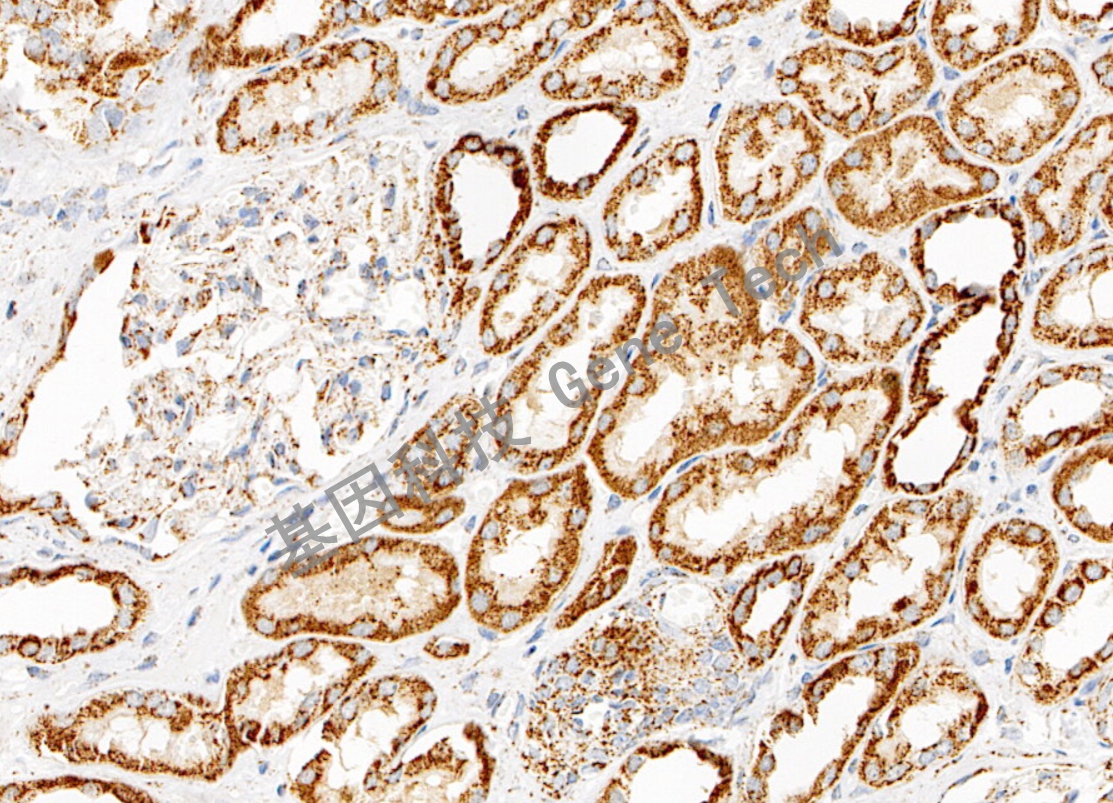

| 腎癌石蠟切片,用 FH(GT2444)染色,細胞漿陽性,DAB 顯色。 | ||

| 預處理:高pH熱修復 | 陽性部位:細胞漿 | 陽性對照:腎癌 |

| 克隆號:J-13 | 種屬:鼠 | 適用染色系統:GTvisionTM |